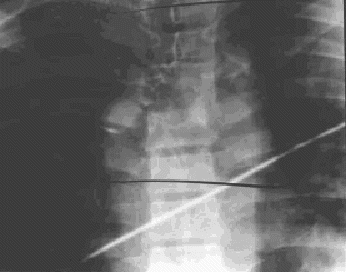

Figura 18.—Radiografía anteroposterior de columna dorsal: No se visualiza el pedículo derecho ni la apófisis espinosa de D4. Desalineación en el plano transversal de las líneas laterales de los cuerpos vertebrales.